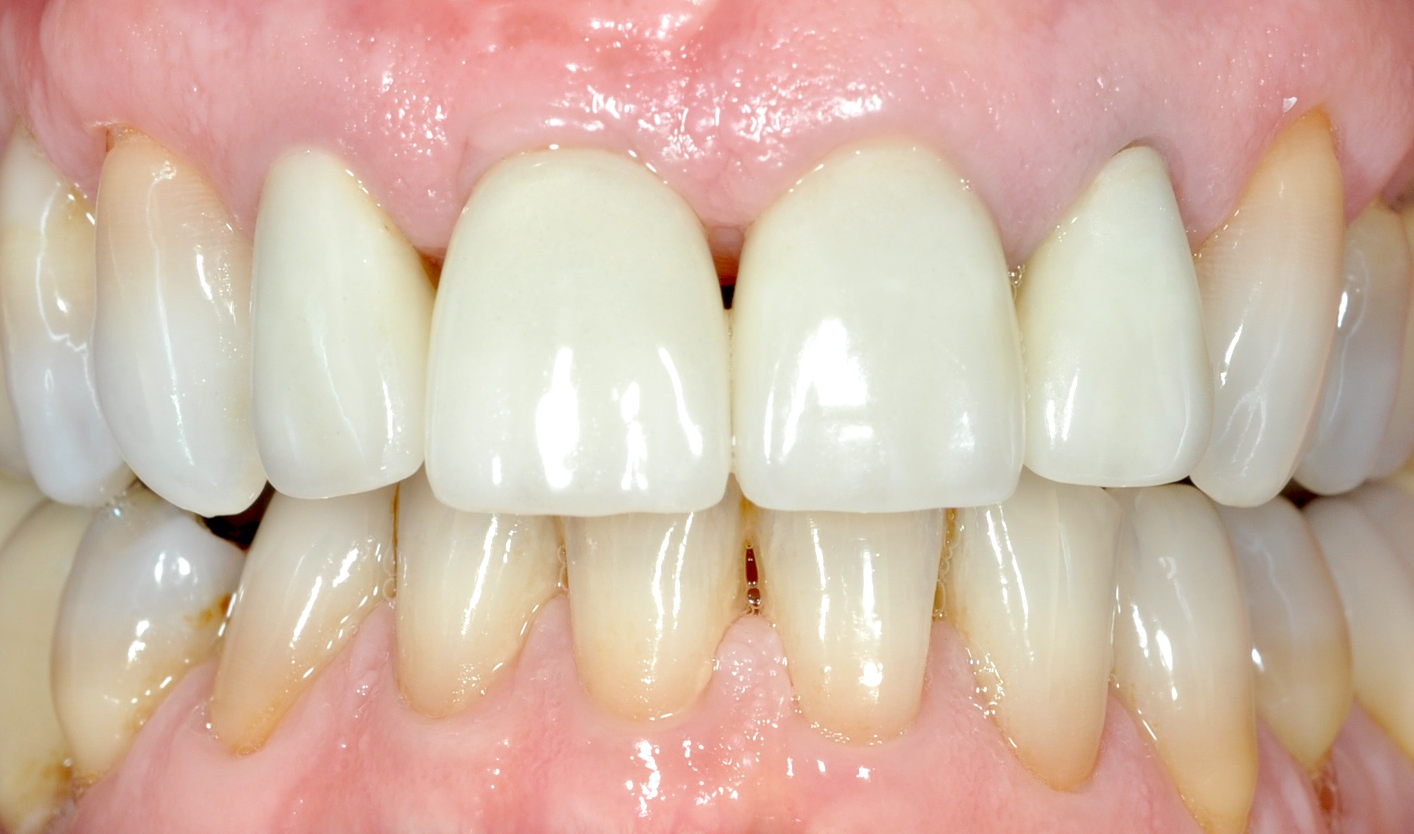

DOPO

Il paziente, quando era ancora bambino, ha subito un trauma sull’incisivo centrale provocandone la necrosi e interrompendo la crescita completa della radice. Il dente è stato curato e riabilitato in modo tale da mantenerlo in arcata per più tempo possibile. A crescita completa del paziente, a causa dello stato precario dell’elemento dentario, si è proceduto con la sostituzione con un impianto osteointegrato.

PRIMA